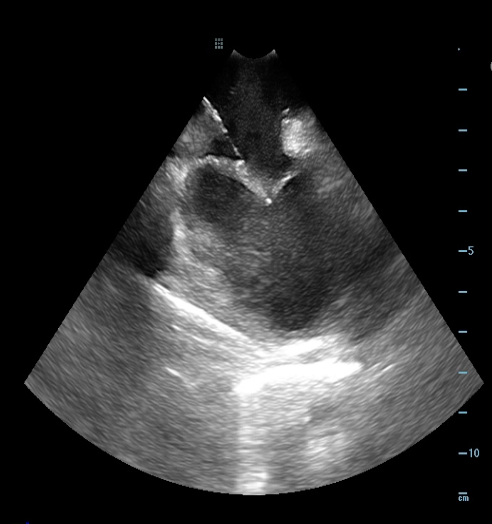

Pulmonary vein isolation in patient with atrial fibrilation. Thank you ADAS3D. Hospital HIGA San Martin. La Plata. Argentina. #ADAS3D #ep #eppeeps #afib